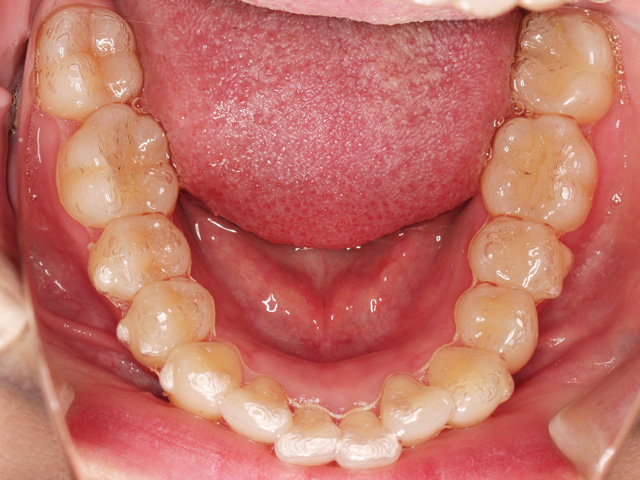

下顎の画像です。上と同じく前歯のスペースが不足しています。

右下の中切歯は「近心捻転(きんしんねんてん)」、左下の側切歯は「舌側転位」と呼ばれる状態になっています。